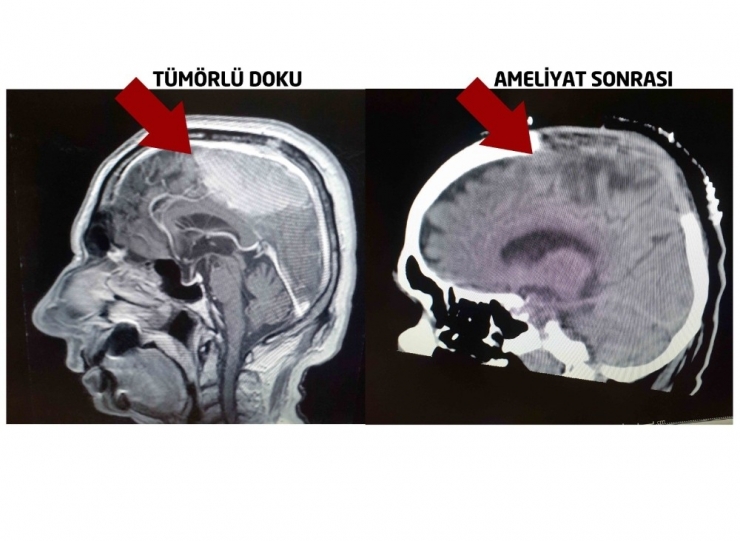

Dr. Öğr. Üyesi Ahmet Eroğlu operasyonla ilgili şu bilgileri verdi: "Hastamız 14 yıl önce beyin tümörü nedeniyle Almanya'da ameliyat olmuş. Beynin ana damar yapılarına yakın olan kısmı ameliyat sırasında riskli olması sebebiyle bırakılmış. Hasta yakınlarına da bu şekilde bilgi verilmiş. Alınmayan tümör gün geçtikçe büyümüş ve hastamız, durdurulamayan sara nöbetleri geçirmeye başlamış. Felç olmuş gibi ayağa kalkamayan Vahit Deveci'nin çekilen MR'ında büyük bir kitle ile karşı karşıya kaldık. Bırakılan kitle 8 cm büyümüş ve kemiğe de sıçramış. Hastanın hayati tehlikesi oldukça yüksekti. Önemli damarsal yapılara yapışıklığı söz konusuydu. Damarsal yapıların tamamından tümörü mikroskobik cerrahi eşliğinde temizledik. Yüksek riskli olan ameliyatı başarı ile gerçekleştirdik. Kontrol filmlerinde en ufak bir tümör artığına saptamadık. Hastamızı ameliyat sonrasında fizik tedavi desteği vererek şifa ile taburcu ettik."